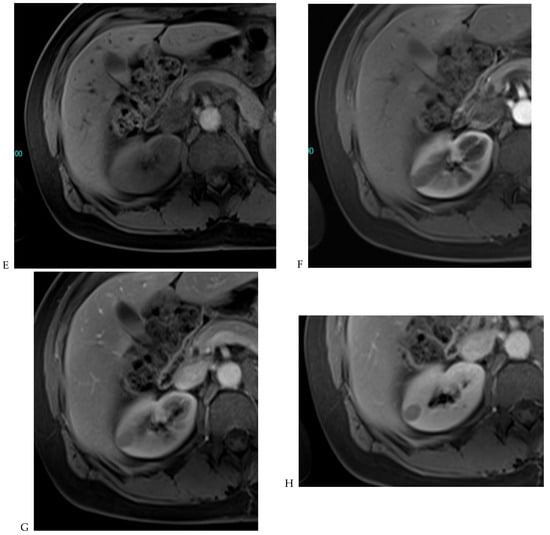

Figure 7.

Papillary renal cell carcinoma in the right kidney of a 75-year-old-woman. (A) Axial T2-weighted fast SE image shows a homogeneous 1.8 cm mass in the posterolateral region of the right kidney, with a lower SI compared to renal parenchyma. Transverse in-phase (B,C) opposed-phase MR images do not show a significant signal loss on the opposed-phase image. (D) The ADC map shows restriction of tumor diffusion into the renal mass. Transverse nonenhanced (E) and gadolinium-enhanced T1-weighted gradient-echo spoiled MR images in (F) corticomedullary, (G) nephrographic, (H) and delayed phase images show progressive enhancement without washout; the mass is hypovascular compared to the renal cortex.